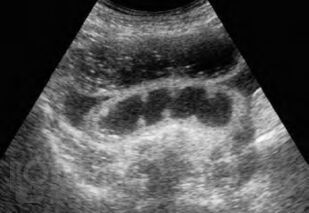

Содержит современные сведения об этиологии, клинической картине, современных аспектах диагностики и лечения несформированных дуоденальных и тонкокишечных свищей.